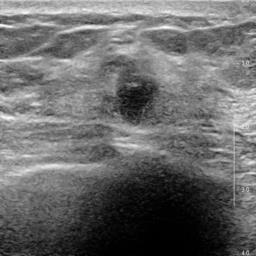

Ultrasonography is an important routine examination for breast cancer diagnosis, due to its non-invasive, radiation-free and low-cost properties. However, it is still not the first-line screening test for breast cancer due to its inherent limitations. It would be a tremendous success if we can precisely diagnose breast cancer by breast ultrasound images (BUS). Many learning-based computer-aided diagnostic methods have been proposed to achieve breast cancer diagnosis/lesion classification. However, most of them require a pre-define ROI and then classify the lesion inside the ROI. Conventional classification backbones, such as VGG16 and ResNet50, can achieve promising classification results with no ROI requirement. But these models lack interpretability, thus restricting their use in clinical practice. In this study, we propose a novel ROI-free model for breast cancer diagnosis in ultrasound images with interpretable feature representations. We leverage the anatomical prior knowledge that malignant and benign tumors have different spatial relationships between different tissue layers, and propose a HoVer-Transformer to formulate this prior knowledge. The proposed HoVer-Trans block extracts the inter- and intra-layer spatial information horizontally and vertically. We conduct and release an open dataset GDPH&GYFYY for breast cancer diagnosis in BUS. The proposed model is evaluated in three datasets by comparing with four CNN-based models and two vision transformer models via a five-fold cross validation. It achieves state-of-the-art classification performance with the best model interpretability.

翻译:超声波分析是乳腺癌诊断的一个重要常规检查,原因是其非侵入性、无辐射和低成本的特性。然而,由于其内在局限性,它仍不是乳腺癌的第一线筛选测试。如果我们能够精确地通过乳房超声图像诊断乳腺癌(BUS),它将是一个巨大的成功。我们提出了许多基于学习的计算机辅助诊断方法,以实现乳腺癌诊断/感官分类。然而,其中多数方法需要事先确定性能模型,然后对ROI内部的跨值进行分类。常规分类支柱,如VGG16和ResNet50等,可以在没有ROI要求的情况下实现有希望的分类结果。但是这些模型缺乏可解释性,从而限制了其在临床实践中的使用。在本研究中,我们提出了一个新的无乳腺癌诊断模型,在超声波图像中进行解释性特征描述。我们利用了先前的解剖学学学知识,即恶性肿瘤和良性肿瘤模型在不同组织层之间有着不同的空间关系,并提议采用状态解析法来编制这一先前的知识。拟议中的HOVer-Trans-Trading-Tradef-trainal Ex-deal-dealal-deal-deal-deal-degraphal-deal-deal-deal-deal-deal-deal disal disal-dal-dal-dal-dal-dal-deal-deal-dal-deal-deal-deal-dal-dal-dal-dal-dal-dal-dal-dal-dal-dal-dal-dal-dal-dal-I-dal-Iversal-dal-Ial-d-d-I-d-d-I-I-I-I-I-I-I-I-I-I-I-I-I-I-I-I-I-I-I-I-I-I-I-I-I-Ial-I-Ial-Ial-I-I-I-I-I-I-I-I-I-I-I-I-I-I-I-I-I-I-I-I-I-I-I-I-I-I-I-I-I-I-I-I-